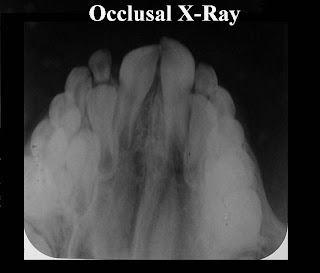

3- Occlusal X-rays .

- Intraoral X-rays are the most common type of dental X-ray taken. These X-rays provide a lot of detail and allow your dentist to find cavities, check the health of the tooth root and bone surrounding the tooth, check the status of developing teeth, and monitor the general health of your teeth and jawbone.

> Types of Intraoral X-Rays ; .